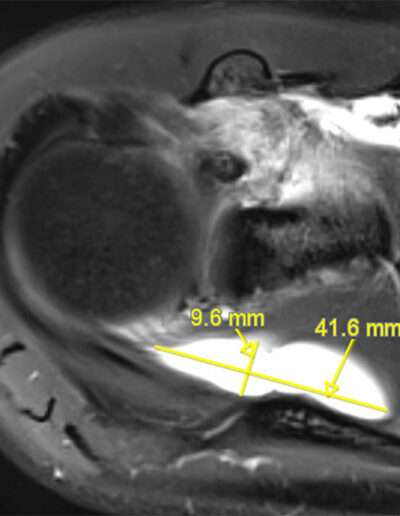

F02: SLAP VIII + MASSIVE COMPRESSIVE CYST ON SSN

Shoulder Right

Patient 39 y/o, Female, Right-hand dominant